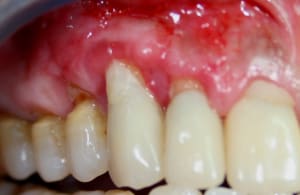

PRE-OP_GREFFE_002_vmfrhj.jpg